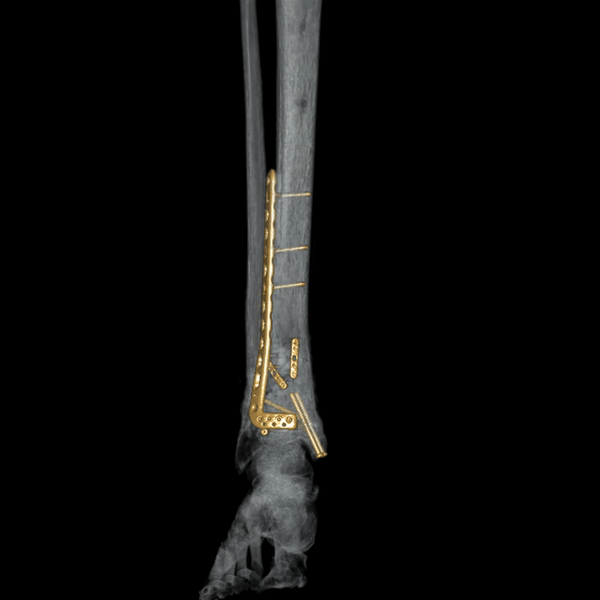

- CT Scan xương khớp. Sử dụng trong các trường hợp chấn thương xương phức tạp, bệnh lý xương: Viêm xương, u xương, di căn xương, lao xương và bất thường bẩm sinh xương.

Ảnh dựng 3D bằng máy CT 160 lát Aquilion Prime SP